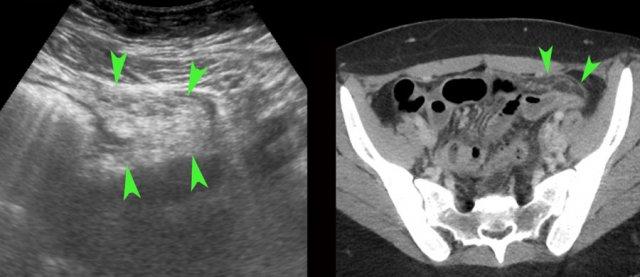

Bệnh nhân mang thai này nhập viện với đau cấp tính hố chậu trái.

Siêu âm phát hiện thai còn nguyên vẹn 8 tuần và ở phía trái tử cung một khối đau, không thể ép xẹp (đầu mũi tên), một phần dạng nang, một phần đặc, nghi ngờ xoắn phần phụ.

Nội soi ổ bụng phát hiện xoắn 360 độ của một nang hoàng thể.

Sau khi tháo xoắn, thành phần dịch lỏng được chọc hút.

Bệnh nhân mang thai 21 tuần được chuyển đến với nghi ngờ viêm ruột thừa. Bệnh nhân đã có các cơn tương tự trước đây.

Siêu âm cho thấy thai còn nguyên vẹn và ở hố chậu phải một nang bì lớn (đầu mũi tên).

Trong quá trình phẫu thuật mở bụng, nang bì bị phù nề, có thể do xoắn từng đợt.

Phẫu thuật cắt nang bảo tồn buồng trứng đã thành công.